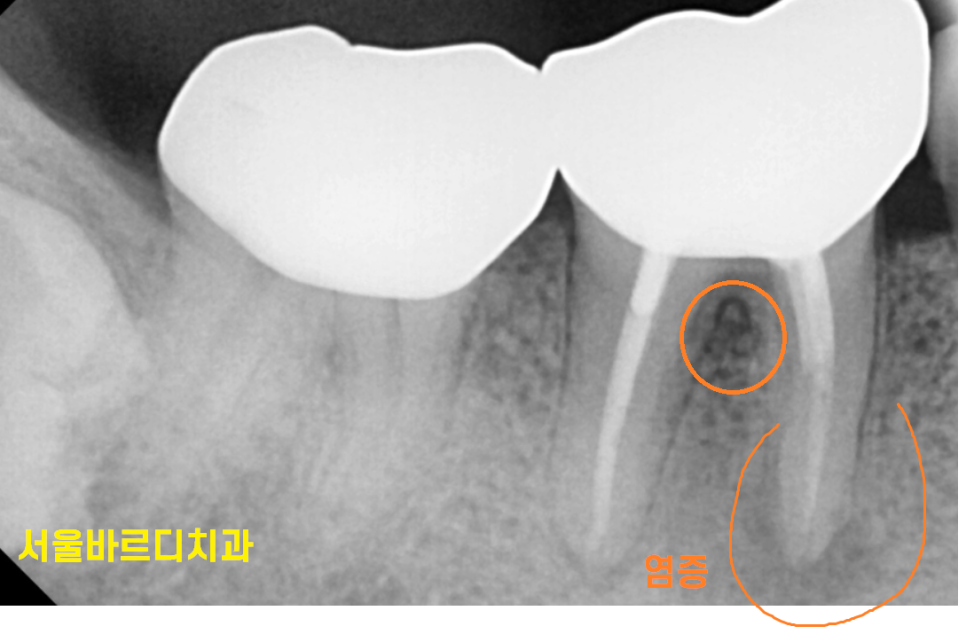

231004

6개월이 되지 않아

뽑을 때가 된 것 같다면서 강일역 치과를 방문해주셨습니다.

이미 뽑아야하는 상황임을 5개월 전에 인지를 하셔서

잇몸 물집이 재발 되었을 때 뽑으러 와주셨어요.

ct를 찍어 얼마나 잇몸뼈가 녹았는지

상태를 보았는데요.

하얗게 차 있어야할 부위가

까맣네요.

염증 지독한 것이

뿌리 모양까지 변화시켰네요.

이전 사진에 비하여 약간 짧아진 게

뿌리까지 흡수되었습니다.